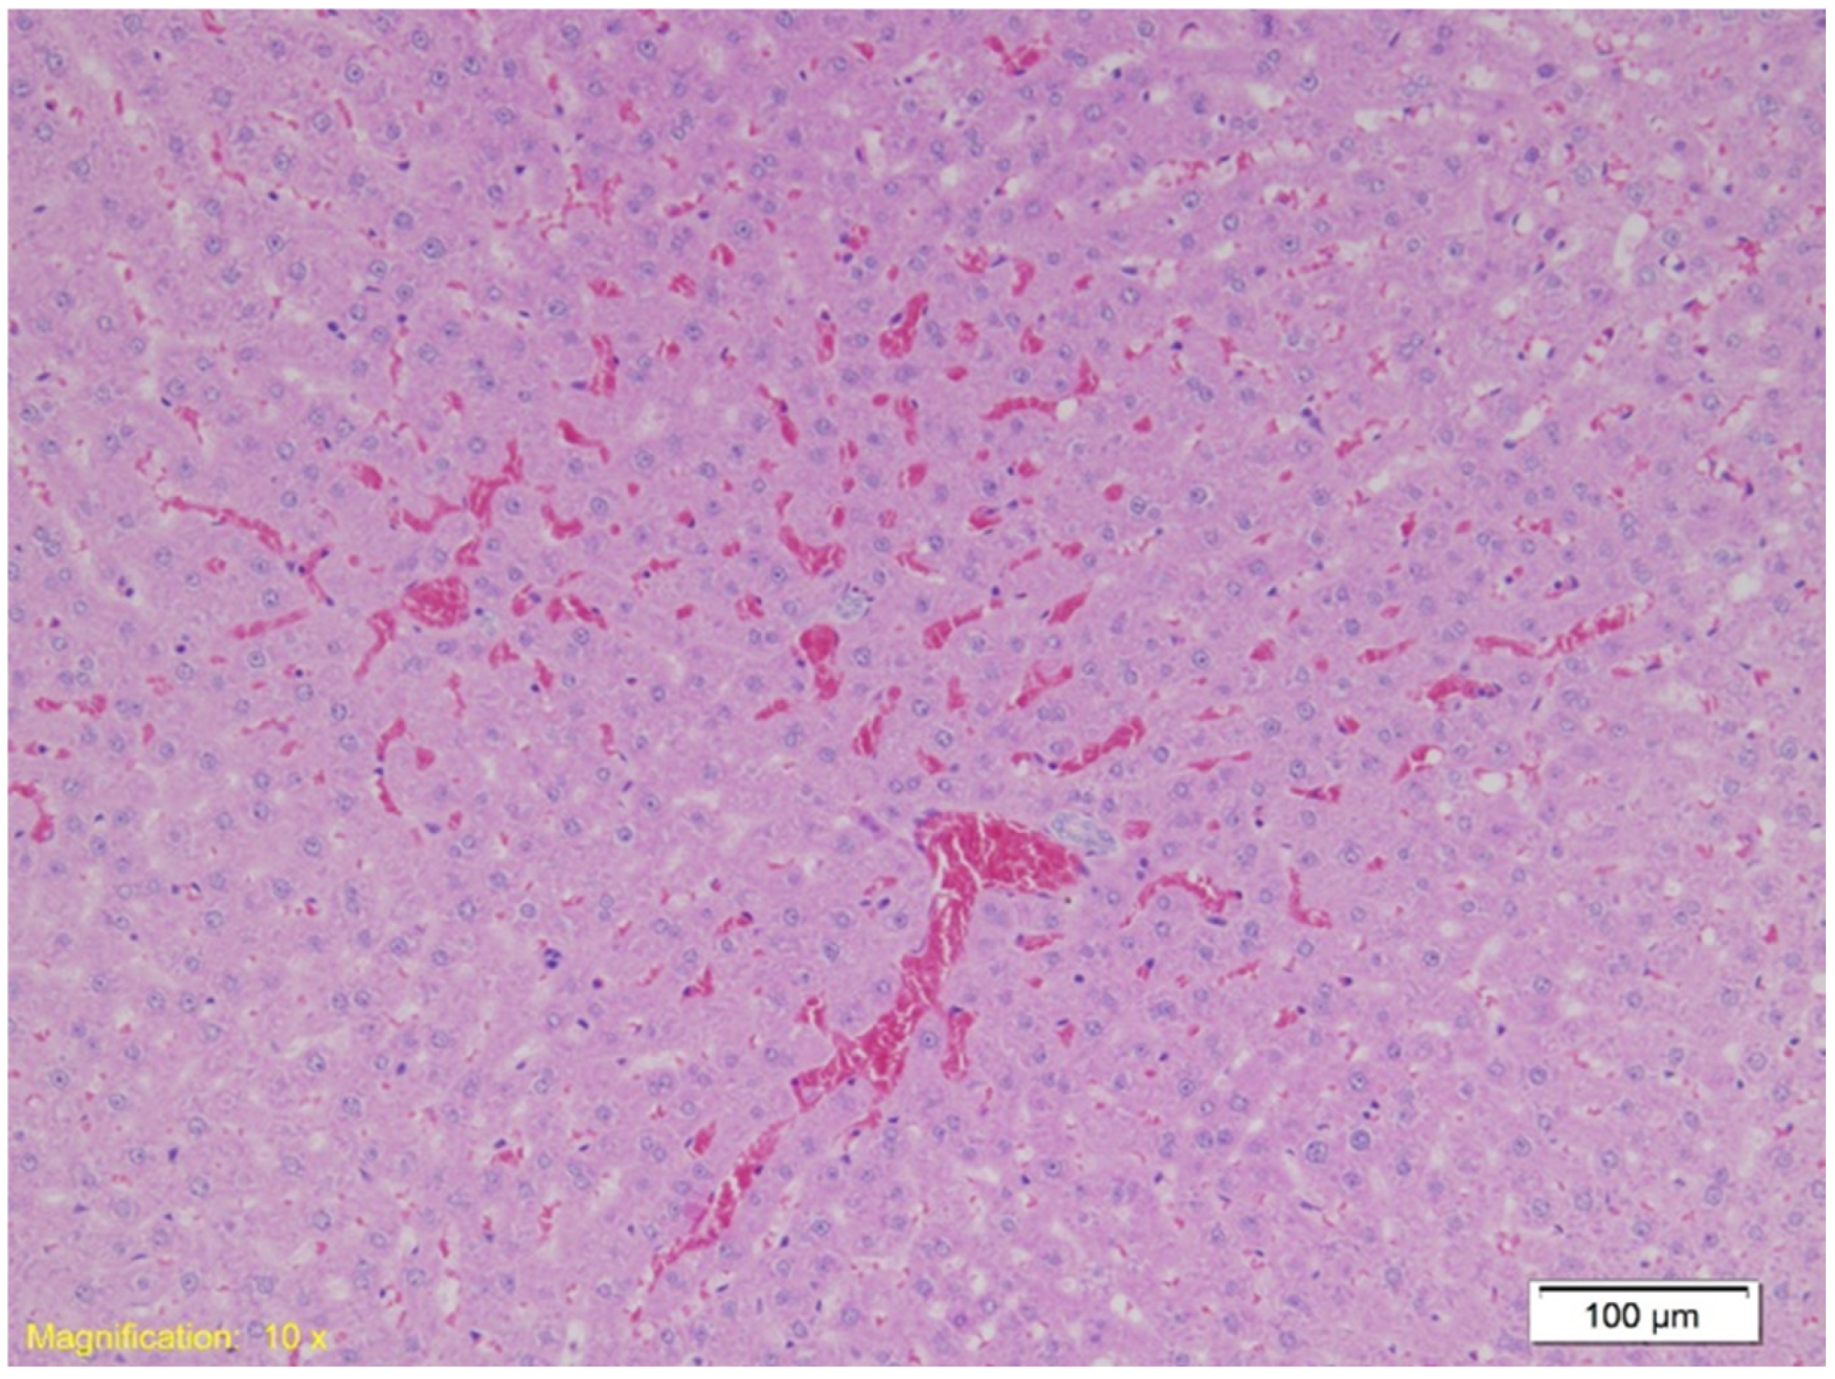

| Organ | Group K (Control) | Group A (Alcohol) | Group B (Benzodiazepine) |

|---|---|---|---|

| Kidney | Hydropic and vacuolar degeneration, congestion; occasional acute tubular injury (eosinophilia, swelling, pyknotic nuclei); minimal lymphocytic infiltrate in interstitium. | Similar findings as Group K; occasional acute tubular injury and lymphocytic infiltrate. | Similar findings as Group K; occasional acute tubular injury and lymphocytic infiltrate. |

| Lungs | Congestion, emphysema, focal atelectasis, and intraalveolar and intraseptal hemorrhage, with emphysema most pronounced. | Slightly increased congestion, intraalveolar and intraseptal hemorrhage; emphysema less pronounced. | Similar to Group A with pronounced congestion, intraalveolar and intraseptal hemorrhage; less emphysema. |

| Heart | Congestion and erythrocyte extravasation in interstitium. | Similar to Group K, with some cardiomyocytes showing finely granular cytoplasm and vacuolar degeneration, suggesting protein denaturation. | Similar to Group K with occasional vacuolar degeneration and protein denaturation in cardiomyocytes. |

| Spleen | Preserved architecture with strong erythrocyte infiltration in red pulp. | Similar findings as Group K. | Similar findings as Group K. |

| Liver | Strong congestion with free erythrocytes in sinusoidal spaces; occasional hepatocyte necrosis with cytoplasmic granulation (potential protein denaturation). | Strong congestion, free erythrocytes in sinusoids; focal hepatocyte necrosis, subcapsular hemorrhage zones. | Strong congestion with similar necrosis and cytoplasmic granulation (suggesting protein denaturation). |

| Gastro-esophagus | Muscle layer hypertrophy, congestion, marked subepithelial eosinophilia. | Similar findings as Group K. | Similar findings as Group K. |